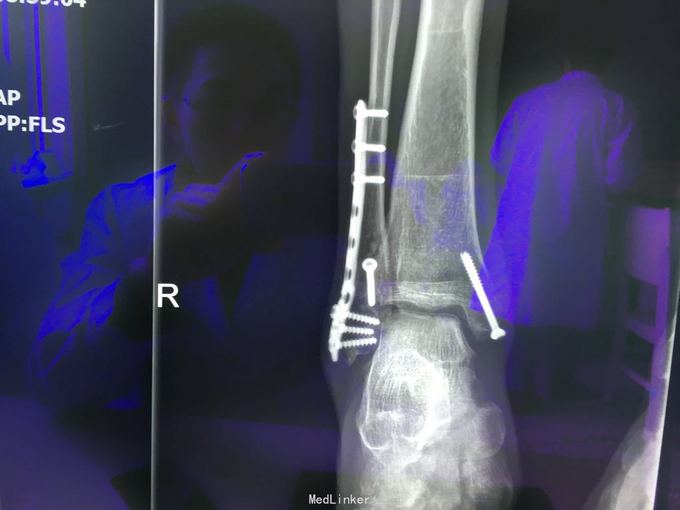

查体:左肾区叩痛,无皮肤隆起,未扪及肿块;腰椎压痛,活动受限,双下肢感觉存在,右小腿石膏托外固定,有踝关节明显肿胀,局部压痛活动受限,指端感觉血运可。 CT及X片:L2、L4椎体爆裂性骨折,L1-L4左侧横突骨折,右坐骨支骨折,右侧胫骨内、后及右侧腓骨外踝骨折,右足第1-4跖骨向外侧脱位及半脱位,伴近端斯脱性骨折。左肾挫裂伤,左肾重度积水,左肾周血肿。

诊断:右足lisfrance损伤,左肾挫裂伤;左肾周血肿,左侧输尿管结石伴左肾重度积水,L2、L4椎体骨折,L1-L4左侧横突骨折,右侧坐骨支骨折,右三踝骨折,全身多处皮肤软组织挫伤 处理:急诊行左肾探查,左肾切除术,择期行经后路腰2、4椎体骨折切开复位、椎公根螺钉内固定术+右内、外踝骨折切开复位内固定术,择期行右足lisfrance关节复位克氏针内固定术。